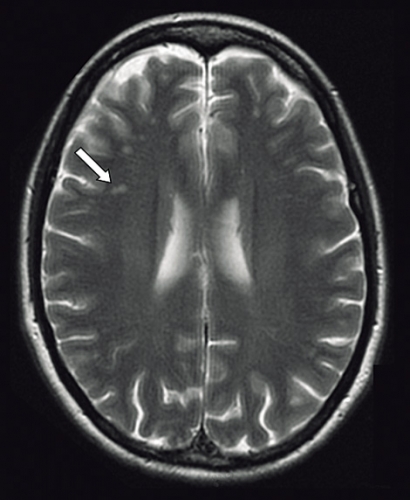

Ny MR-undersökning visade på oförändrad bild med förändringar i vit substans utan säker patologisk signifikans (Figur 1). På den kliniska bilden av limbisk encefalit genomgick patienten DT torax och buk, som inte visade på tumör.